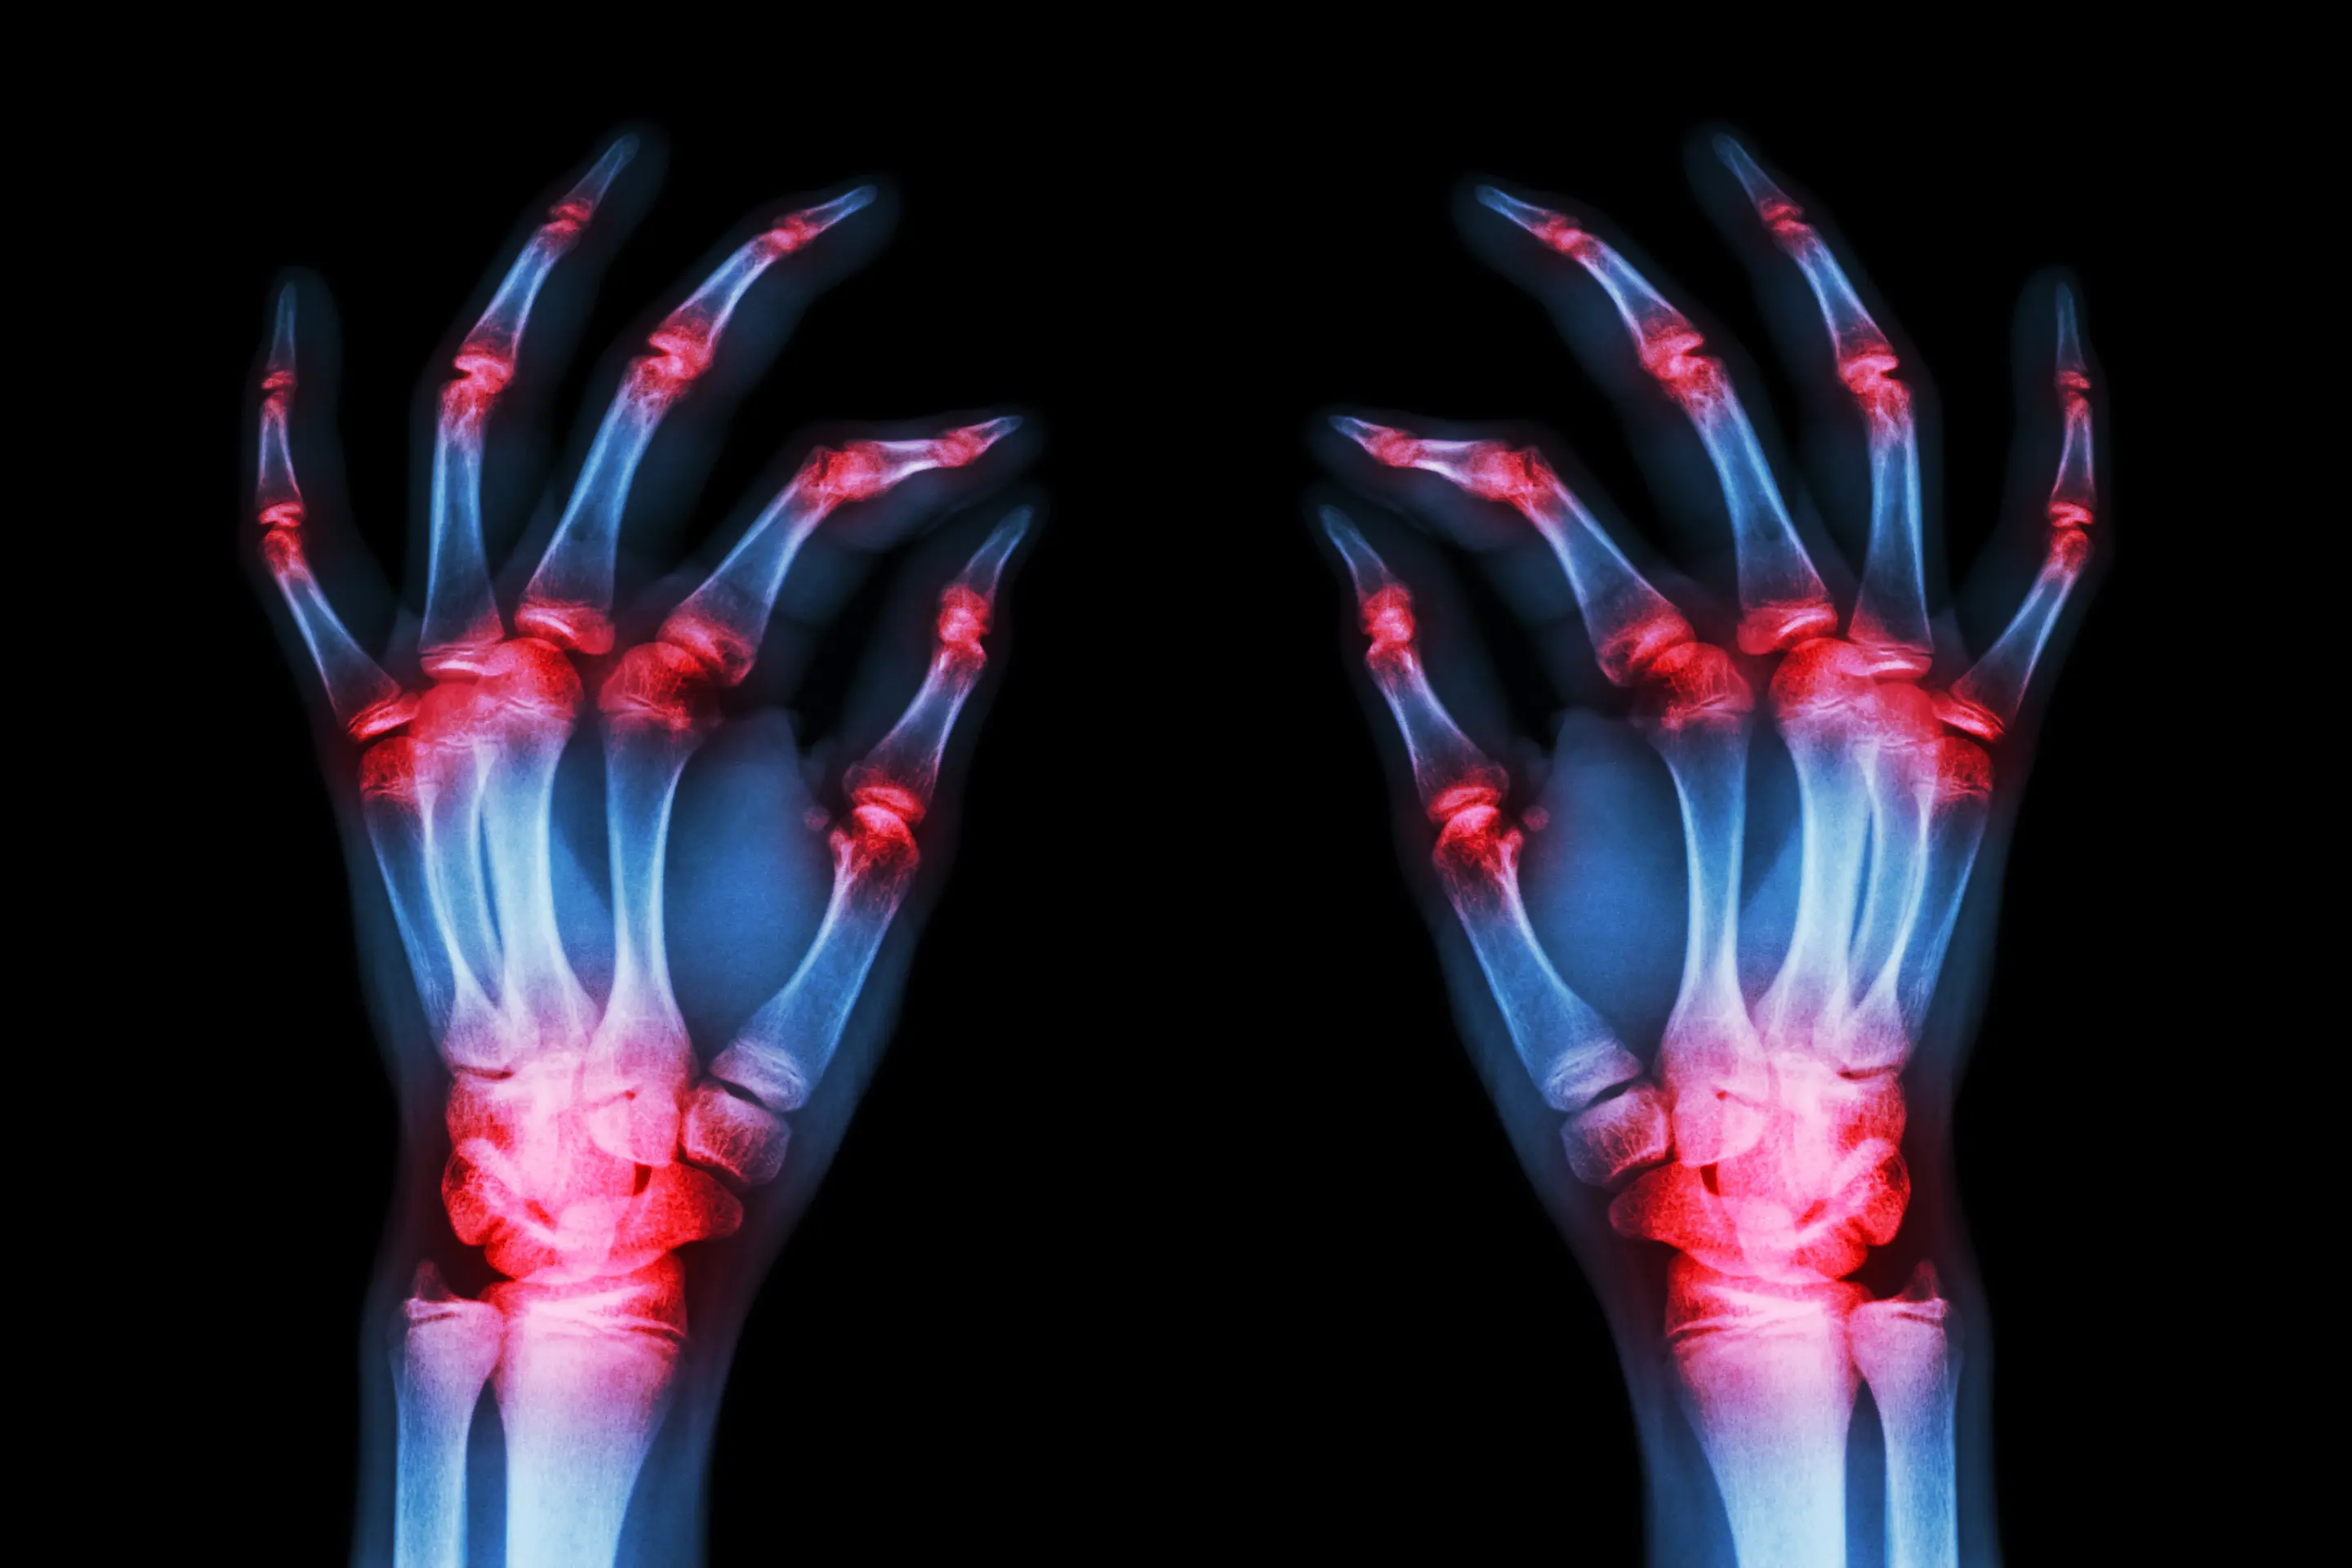

In the realm of medical research, the integration of advanced technologies has ushered in a new era of precision healthcare. Among these cutting-edge tools, machine learning (ML) algorithms stand out as formidable assets in predicting and managing various health conditions. A recent study published in Nature Scientific Reports sheds light on the promising role of ML in predicting osteoporosis among patients with rheumatoid arthritis (RA), offering insights that could revolutionize clinical practices.

Led by Chaewon Lee and colleagues from Kangwon National University in South Korea, the study addresses a critical gap in existing research by focusing on the application of ML algorithms specifically tailored to the unique characteristics of RA patients. While ML has been extensively employed in diverse clinical settings, its potential in predicting osteoporosis among RA patients remained largely unexplored until now.